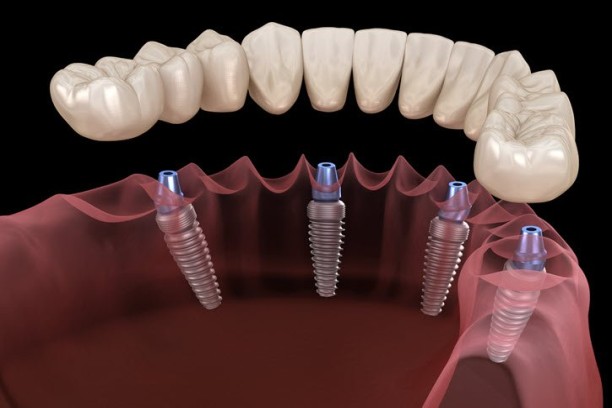

Implants

Permanent, natural-looking replacement for missing teeth using dental implants.